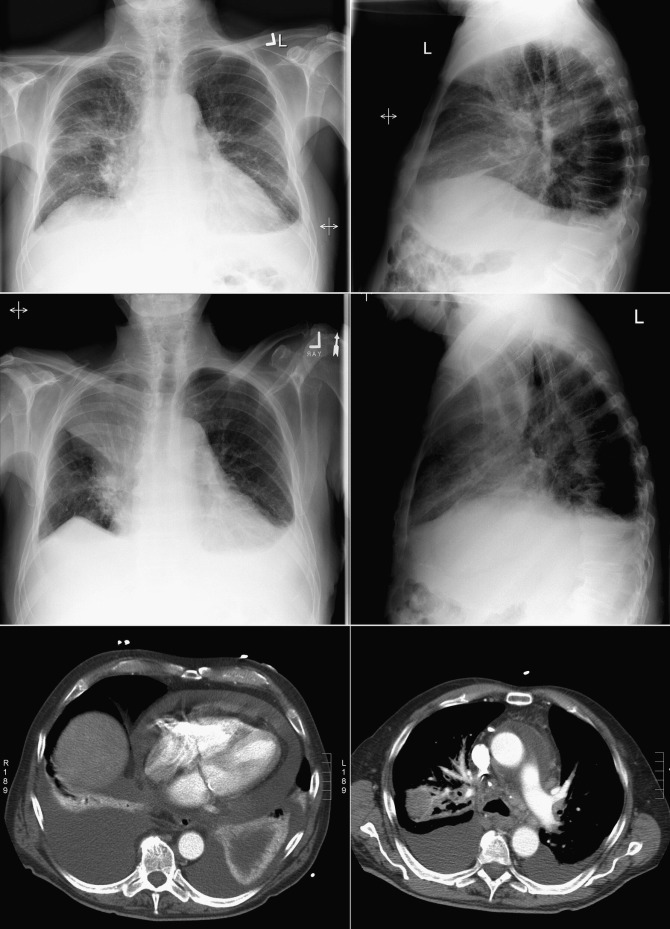

Constrictive Pericarditis

In constrictive pericarditis ( Graphic 16-1 ; Figs. 16-16 to 16-23 ) , the CPS is usually nonspecifically and mildly enlarged. Occasionally, the heart is normal or small in size. The left atrium is the most frequently enlarged chamber, because its enlargement is less restricted by pericardium. The right atrial contour on the frontal chest radiograph may be flattened. Calcification of the pericardium suggests past tuberculosis, but since tuberculosis has become uncommon at most centers, 90% of cases of constrictive pericarditis are currently noncalcified. Calcification, especially diaphragmatic, is not specific for constrictive physiology; it may be seen in the absence of cardiac compression. The apical surface is less frequently calcified than the interventricular and atrioventricular grooves. The apex seldom calcifies prominently in constrictive pericarditis; this finding suggests a calcified apical aneurysm rather that constrictive pericarditis.